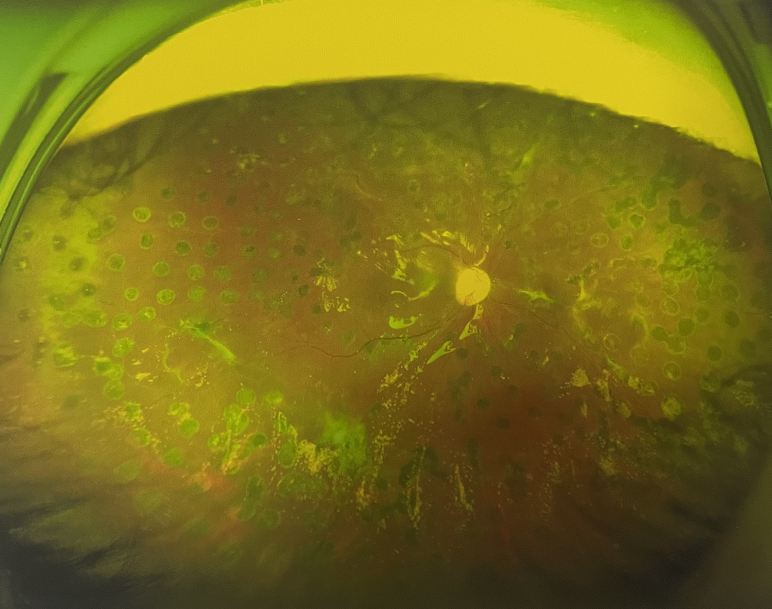

右眼術(shù)后

張小虎醫(yī)生為王女士進(jìn)行右眼玻璃體腔注藥術(shù),3天后進(jìn)行右眼23G玻璃體切割術(shù)后視力有所提升。

4個月后王女士來院取硅油,取油后視力恢復(fù)到0.6。“當(dāng)時來的時候真的只能看到模糊的影子,特別害怕覺得完了,想說眼睛估計(jì)要瞎了,沒想到手術(shù)后視力竟然提升了,現(xiàn)在也看得比較清楚了。”王女士說到。

張小虎醫(yī)生表示,糖網(wǎng)病進(jìn)展到嚴(yán)重增殖期帶來的視力損傷往往是極其嚴(yán)重的,目前王女士右眼從術(shù)前0.02恢復(fù)到術(shù)后0.6,已屬十分難得。